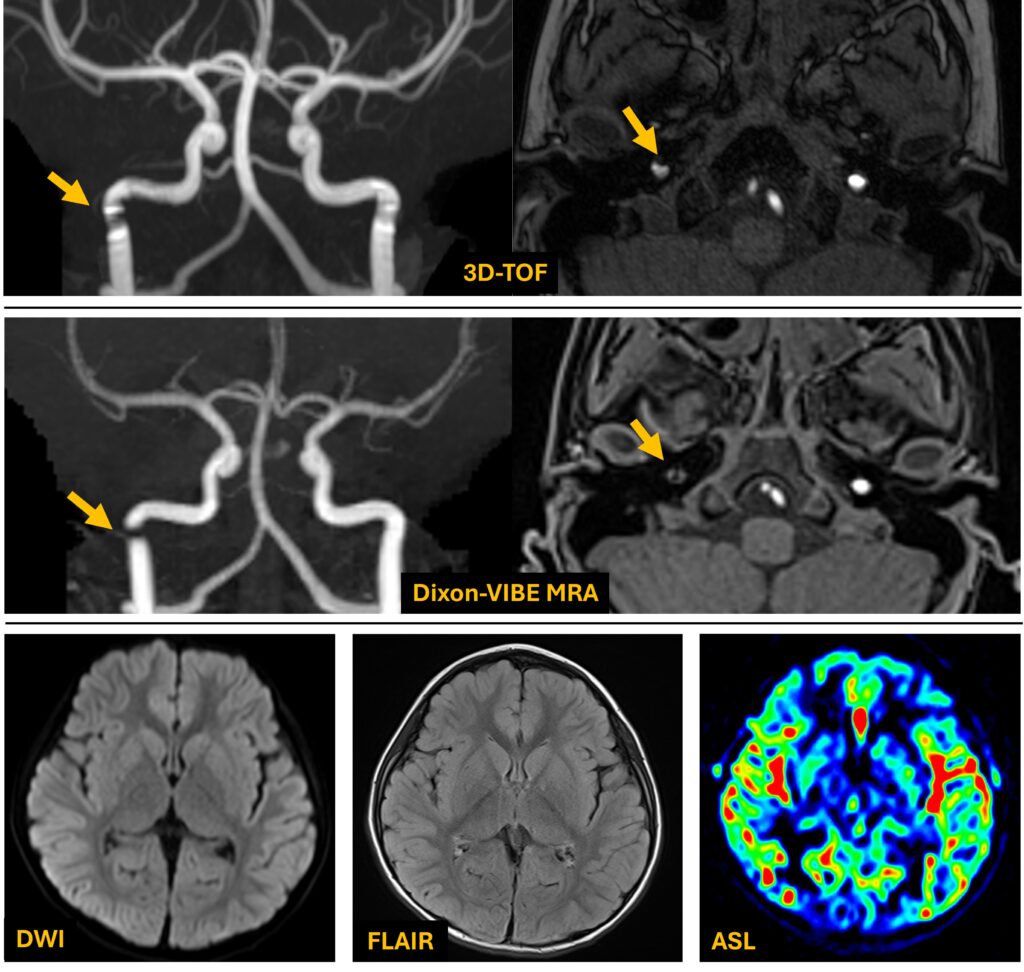

先日遭遇した小児てんかん疑いの症例のご紹介をしたいと思います。TOFで右内頚動脈に狭窄様所見があります。スラブの繋ぎ目の影響を疑いDixon-VIBE MRAを追加撮像しました。こちらでも同部位に欠損が見られましたので、これは実際に狭窄している症例?と思ったのですが、MRA以外に全く所見が見られなかったのが気にかかりました(Fig4)。

念のためDixon-VIBE MRAの元画像(Opp-Phase)を確認したところ、まったく狭窄が無いことが判明しました(Fig5)。当院では頭頚部の造影後3D撮像にもDixon-VIBEを多用していますが、Dixon計算エラーの経験はありませんでした。この症例はおそらく、屈曲部での乱流とスラブの境目が複合的に影響して血管内部で位相分散を起こしたものと予想されます。Dixon-VIBE MRAではWater画像以外あまり見る習慣がなかったことと、頭部では計算エラーは起こらないと高を括っていた自分にとっては、反省とともに大変勉強になった症例でした。本手法が皆様の日々の診療に少しでもお役に立てれば幸いです。最後までお読み頂きありがとうございました。